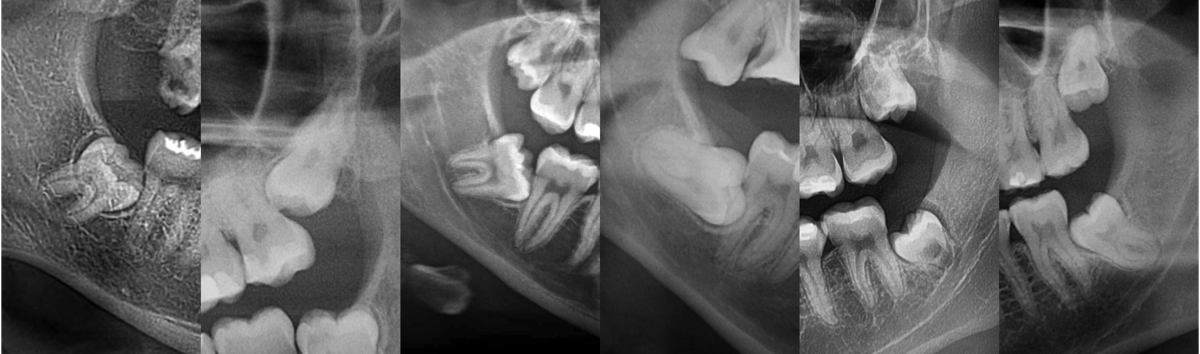

Pacjent 4

Leczenie próchnicy pierwotnej zębów bocznych (próchnica powierzchni stycznej zębów trzonowych która spowodowała odłamanie listwy brzeżnej) w zębie pierwszym trzonowym.

Odbudowa z odtworzeniem naturalnej morfologii zęba nowoczesnym materiałem światłoutwardzalnym 3M™ Filtek™ BulkFill One oraz Filtek Universal zapewniające nieporównywalną trwałość w czasie i odporność mechaniczną.

Leczenie zachowawcze odbywało się w osłonie koferdamu zapewniającej komfort pacjenta i suchość pola zabiegowego.